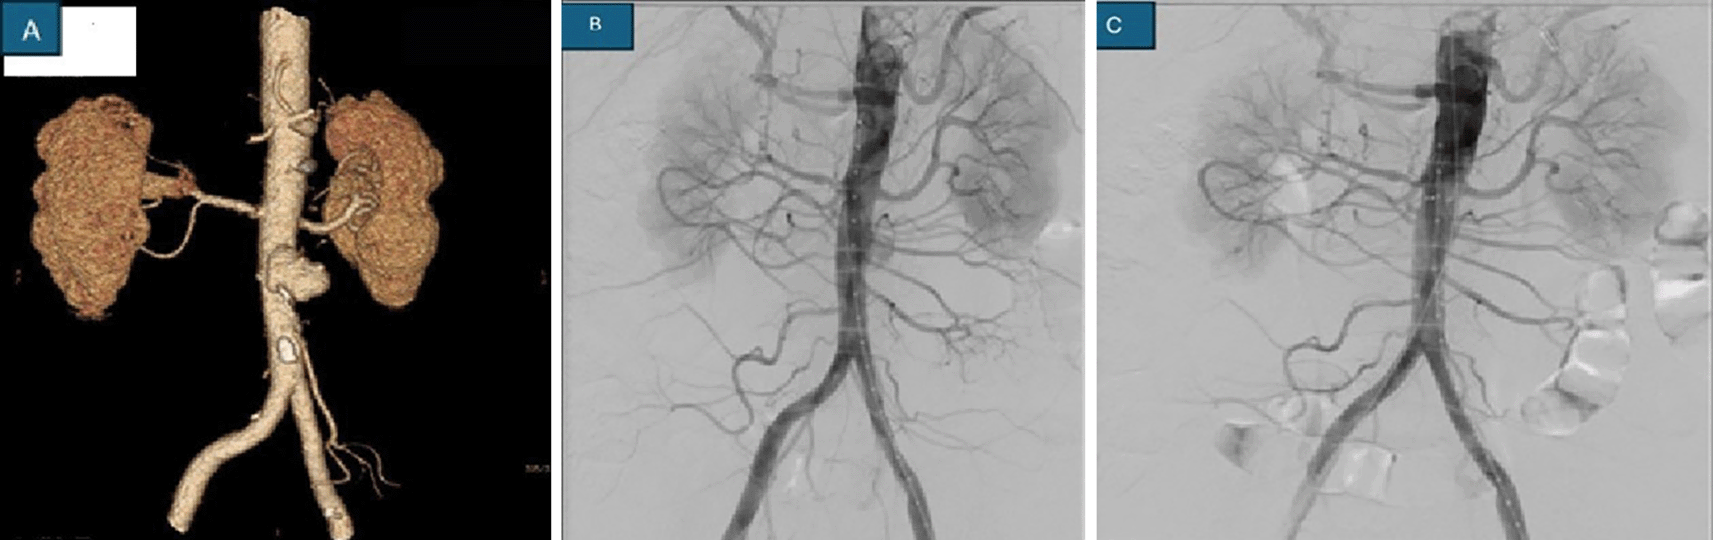

The size of the aneurysms was small (<5 mm) in 3 patients, whereas large aneurysms were noted in the remaining 6 patients. All these patients had elevated C-reactive protein levels and ESRs. No immediate postoperative complications were observed. The sources of these postinfectious aneurysms were bacterial or fungal in origin ( Table 2). The identification was based on blood culture or GeneXpert for tuberculosis or fungal culture results. CT angiogram, digital subtraction angiography (DSA) or ultrasonography are considered important diagnostic tools ( Table 1) ( Figure 1).

A study by Alawieh et al reported that 44.2% of IIAs were small in size (<5 mm), 56.9% were traced in the MCA, and 13.1% were traced in the PCA.9 Prompt recognition of these cases is an effective tool for the management of postinfectious aneurysms. Timely diagnosis of a mycotic TAAA requires a high index of suspicion in patients presenting with fever, headache, back pain, pain abdomen, or a pulsatile abdominal mass.4,10 In our study, TAAA patients presented with similar symptoms, namely, acute onset of fever and abdominal pain followed by hypovolemic shock. Although leucocytosis and elevated erythrocyte sedimentation rates are common, these findings are nonspecific and can often lead to delayed or incorrect diagnoses. Many a times blood cultures may be negative for bacteraemia, especially if there is before antibiotic administration. Contrast-enhanced computed tomography can suggest infective features, such as an atypical setting of the aneurysm; a multilobulated, multifocal or saccular configuration; lacking calcification in the aneurysmal wall; gas in the periaortic area with a soft tissue reaction; and adjacent vertebral osteomyelitis. In uncertain cases, Gallium-67 isotope scanning may help in localizing the active infectious process and with a hold on septic foci at other site. Angiography, when feasible, is useful tool for defining the anatomy of the visceral vessels and aiding in preoperative planning. Even if noninvasive tests are negative, DSA remains the yardstick and is recommended for the detection of IIAs.11,12